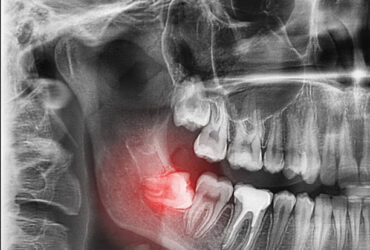

ฟันคุดคือ ฟันกรามซี่ในสุด ทั้งหมด 4 ซี่ บน ล่าง ซ้าย ขวา ไม่สามารถขึ้นได้ตามปกติเพราะพื้นที่ไม่เพียงพอให้ฟันสามารถขึ้นมาได้ บางซี่อาจจะโผล่ขึ้นมาเล็กน้อย และบางซี่ถูกฝั่งอยู่ในกระดูดขากรรไกร อาจจะขึ้นตรง เอียงหรือนอนในแนวราบส่วนใหญ่ฟันคุดมักพบว่าอยู่ที่ฟันกรามซี่ล่างในสุดและพบมากสุดในช่วงอายุ ประมาณ 16 – 25 ปี หรืออาจจะช้ากว่านั้น